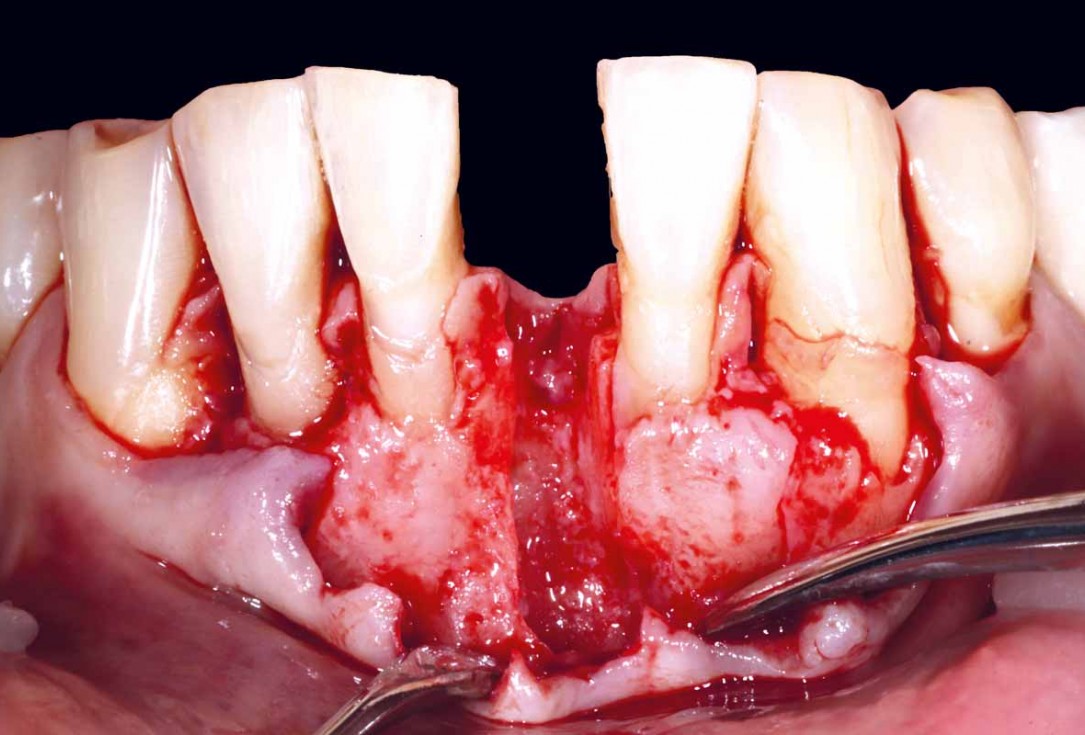

Pre-operative situation showing tooth 21 with deep periodontal pocket. Tooth presented with mobility grade III.